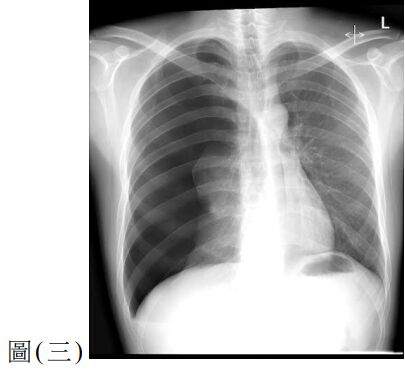

10. 一位60歲女性因腹痛、噁心與嘔吐來急診。此病人有剖腹產與膽囊切除手術病史,其 KUB如圖(二),請問最有可能的診斷為何?

(A) 沾黏性小腸阻塞( adhesive small bowel obstruction ) (B) 大腸阻塞(large bowel obstruction ) (C) 缺血性大腸炎(ischemic colitis) (D) 小腸憩室炎(small bowel diverticulitis)